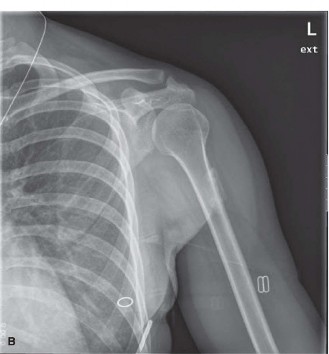

The diagnostic workup for suspected myositis ossificans relies heavily on the temporal evolution of radiographic findings, which mirror the histological maturation of the heterotopic bone. Initial plain radiographs of the left femur and knee (anteroposterior and lateral projections) obtained in the emergency department immediately following the initial trauma were entirely unremarkable. They demonstrated normal osseous architecture with no evidence of acute fracture, periosteal reaction, or abnormal soft tissue radiodensities.

Follow-up radiographs obtained at six weeks post-injury, coinciding with the clinical emergence of the palpable mass, revealed subtle, amorphous, flocculent calcifications within the soft tissues of the anterior thigh. These early calcifications were ill-defined and lacked a distinct trabecular pattern, representing the early osteoid formation phase.

Figure 1: Initial radiograph demonstrating early, ill-defined soft tissue calcification within the quadriceps muscle, approximately 6 weeks post-trauma.

By the twelve-week mark, repeat radiographs demonstrated a dramatic evolution. The lesion exhibited a highly organized pattern of ossification characterized by a distinct, mature, radiodense peripheral rim surrounding a more radiolucent, immature center. This centrifugal pattern of maturation is the classic radiographic "zone phenomenon" that is virtually pathognomonic for myositis ossificans. Crucially, orthogonal radiographic views confirmed a distinct radiolucent cleft separating the ossified mass from the underlying femoral cortex, with absolutely no evidence of cortical destruction, endosteal scalloping, or aggressive periosteal reactions (such as Codman's triangle or sunburst appearance), which strongly militated against a primary malignant bone tumor.